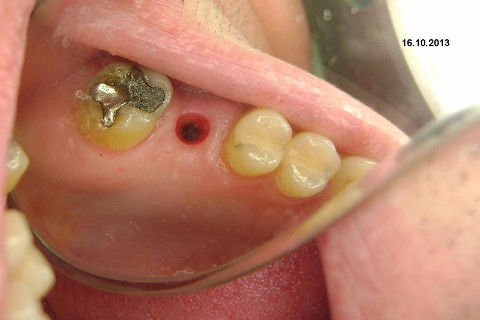

Instalação de um implante em região do 26. Utilizamos um implante cone morse Alvim Neodent 4.3 X 11,5. Foi uma cirurgia muito rápída e minimamente traumática, sem retalho e sutura.